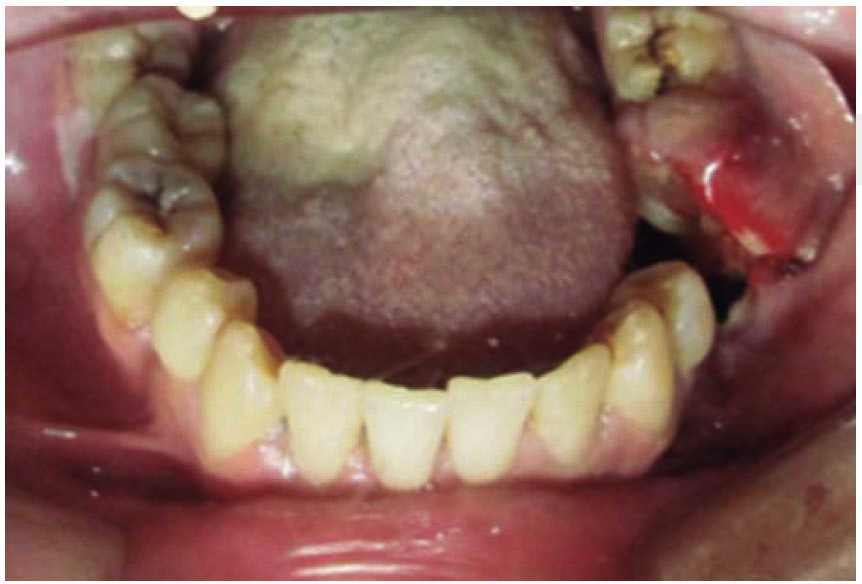

Masculino de 30 años con diagnóstico de fractura de cuerpo mandibular izquierdo por proyectil de arma de fuego. Sufre agresión en una riña al salir de un centro de diversión nocturna y es disparado a cuatro metros de distancia. A la exploración se presenta edema a nivel cervical, tercio medio e inferior facial, orificio de entrada en región geniana izquierda y orificio de salida a nivel submandibular derecho (Figura 4). Intraoralmente con herida en proceso alveolar mandibular en línea de fractura y ausencia de piezas dentales (Figura 5). Se inicia bajo anestesia general tratamiento con estabilización de la vía aérea mediante traqueotomía. A nivel local se realiza desbridamiento de bordes de herida, lavado con jabón quirúrgico, solución fisiológica y sutura de herida. Al terminar el tratamiento de tejidos blandos se busca estabilidad inicial oclusal con arco barra tipo Erich. El paciente permanece hospitalizado bajo un esquema terapéutico de inmunización, antibiótico y analgésico.

En los tres casos presentados se inicia con valoración cardiopulmonar, manejo de vía aérea, control hemodinámico, ventilación, discapacidad neurológica y daños específicos.9-11 Con la exploración física determinamos la extensión de daño en los tejidos, presencia de orificios de entrada y salida para descartar la presencia de bala al interior en una cavidad o tejido (caso 2). El manejo maxilofacial se inicia con desbridaje conservador, lavado, extracción de restos radiculares, sutura y estabilización oclusal. La reducción y fijación de las fracturas (caso 1 y 3) se realizó en un segundo acto quirúrgico con placas de reconstrucción. En los casos expuestos se observó una buena evolución, una cicatriz ósea favorable y la necesidad de continuar con una rehabilitación oral mediante prótesis o implantes osteointegrados. Las complicaciones y secuelas son comunes y surgen por lo general a causa de la severidad de las lesiones iniciales, retraso en el tratamiento por riesgo vital o estado sistémico del paciente.